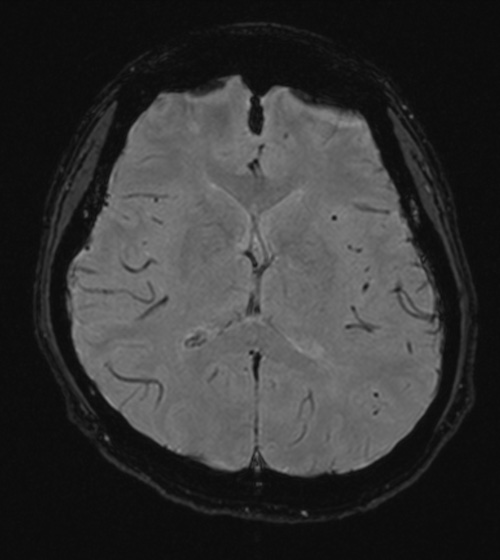

MRIとは、(MRI=MagneticResonanceImaging:磁気共鳴画像診断装置)の略です。MRIは、強力な磁石でできた筒の中に入り、強い磁石とラジオに使われているような電波を用いて体内の状態を画像にする検査です。特に脳や脊椎、四肢、子宮、卵巣、前立腺といった骨盤内の病変に関して優れた検出能力を持っています。

| 撮影可能な部位 | 頭部、脊椎、乳腺、腹部、骨盤部、関節など 全身領域 |

頭部MRI検査において、脳萎縮評価システムVSRADを用いた解析も行

っております。

MRI検査依頼書(PDF)当院で撮影したMRI画像